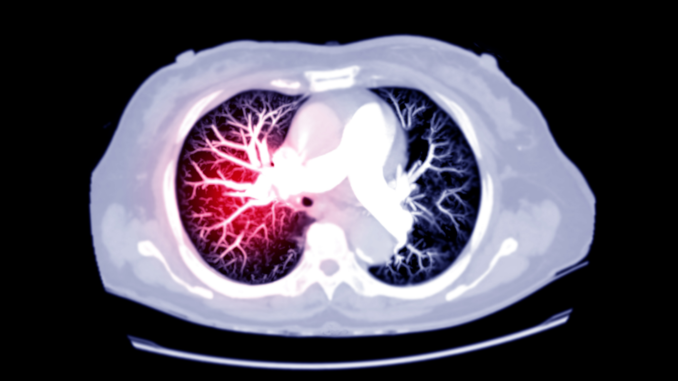

Corona-Infizierte haben einer Studie zufolge bis zu ein halbes Jahr nach der Ansteckung ein erhöhtes Risiko für die Bildung schwerer Blutgerinnsel. Der am Donnerstag in der Fachzeitschrift „BMJ“ veröffentlichten Studie zufolge hatten die Infizierten auch sechs Monate nach der Infektion noch ein 33-fach erhöhtes Risiko für eine Lungenembolie, bei der ein Blutgerinnsel Arterien in der Lunge blockiert.

Auch die Gefahr einer tiefen Venenthrombose – ein Blutgerinnsel, das normalerweise in den Beinen entsteht – war bis zu drei Monate nach der Infektion mit dem Coronavirus um das fünffache erhöht. Menschen mit einer schweren Covid-Erkrankung oder Vorerkrankungen waren besonders gefährdet. Aber auch bei Personen mit leichten Erkrankungen, die keinen Krankenhausaufenthalt erforderten, war die Gefahr einer Lungenembolie und einer tiefen Venenthrombose höher.